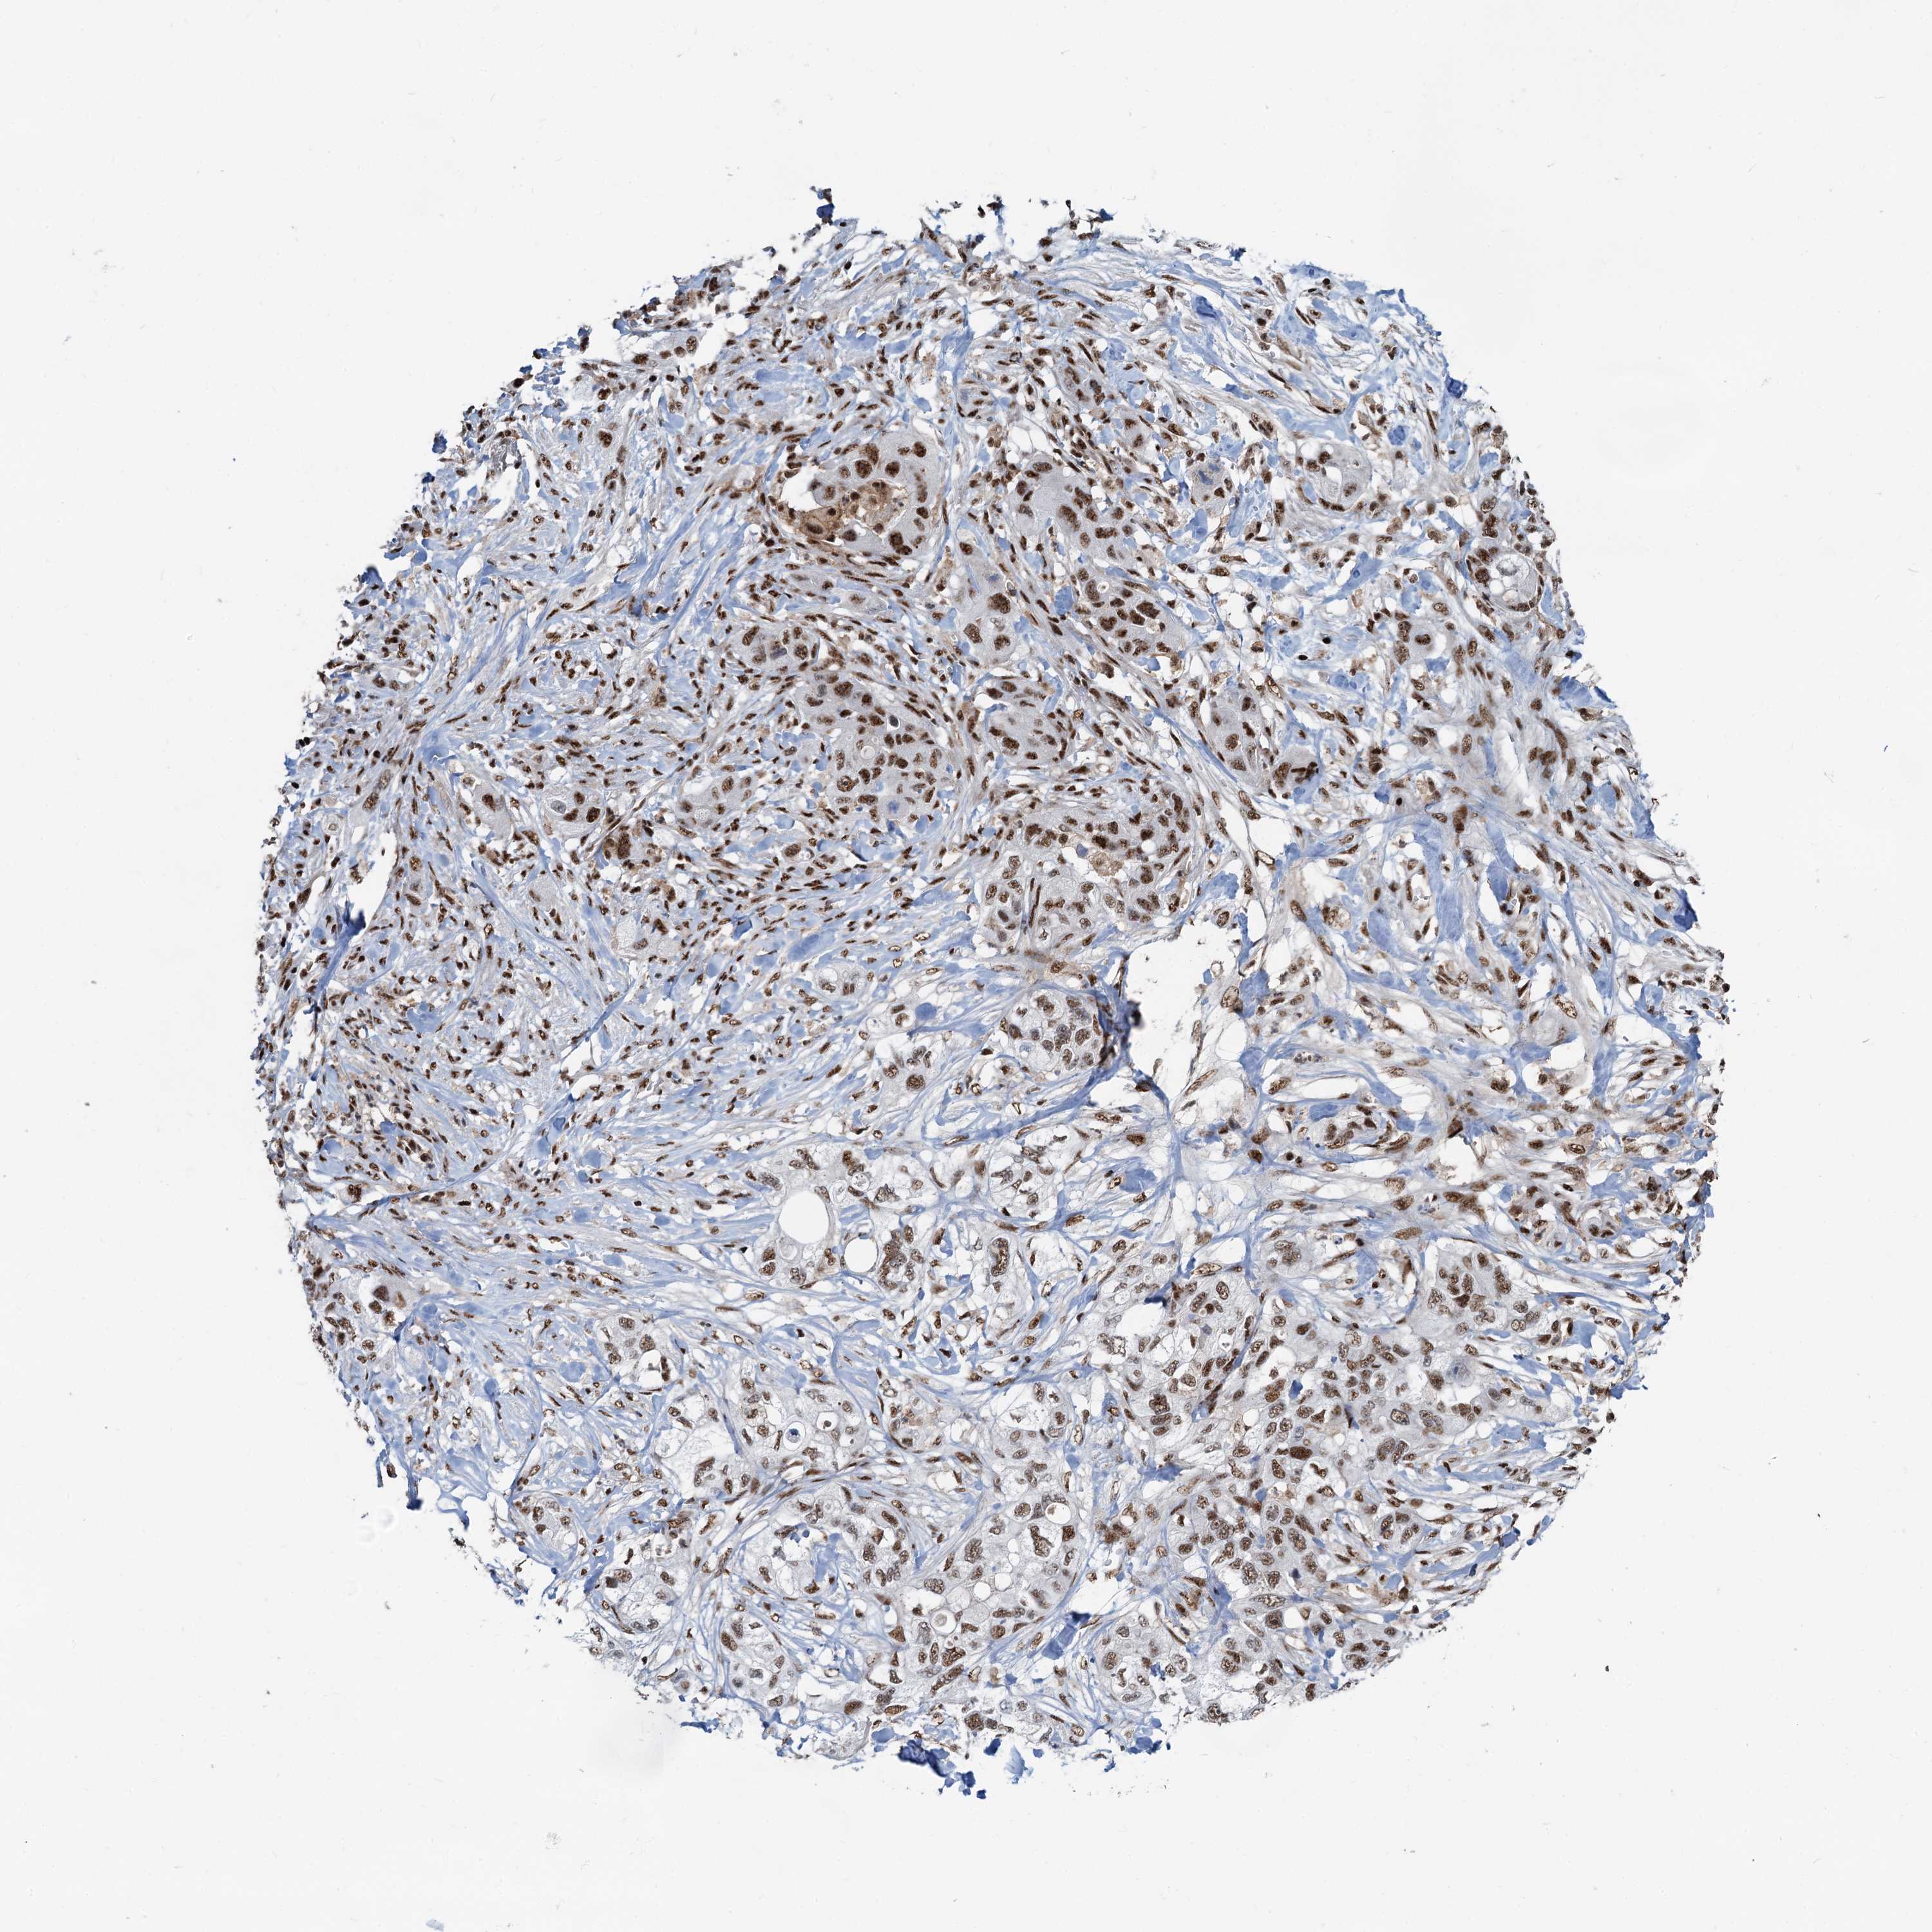

PANCREATIC CANCER - Protein expressioni

A mouse-over function shows sample information and annotation data. Click on an image to view it in a full screen mode. Samples can be filtered based on level of antibody staining by selecting one or several of the following categories: high, medium, low and not detected. The assay and annotation is described here.

Note that samples used for immunohistochemistry by the Human Protein Atlas do not correspond to samples in the TCGA dataset.

Antibody stainingi

Antibody staining in the annotated cell types in the current human tissue is reported as not detected, low, medium, or high, based on conventional immunohistochemistry profiling in selected tissues. This score is based on the combination of the staining intensity and fraction of stained cells.

Each image is clickable and will lead to virtual microscopy that enables deeper exploration of all samples and also displays staining intensity scores, fraction scores and subcellular localization as well as patient and tissue information for each sample.

Antibody HPA040252

Staining

High

Medium

Low

Not detected

Intensity

Strong

Moderate

Weak

Negative

Quantity

>75%

75%-25%

<25%

None

Location

Nuclear

Cytoplasmic/membranous

Cytoplasmic/membranous,nuclear

Adenocarcinoma, NOS